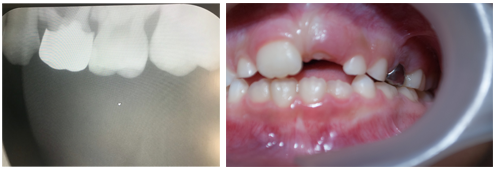

Paediatric Dentist | All Smiles In Finchley

www.allsmiles.org.uk paediatric fillings caries appears

www.allsmiles.org.uk paediatric

Dentist gained handan vast. Finchley train travel visiting. Paediatric fillings caries appears